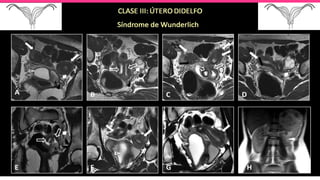

SINDROME DE WUNDERLICH

(11% de las anomalías del conducto de Müller)

• 30% están asociadas a anomalías del tracto renal .

• Su etiopatogenia es desconocida .

• Se propone una nueva clasificación de este síndrome debido a las

características clínicas que difieren según el nivel de obstrucción completa

e incompleta del septum vaginal, permitiendo un diagnóstico oportuno y

tratamiento eficaz